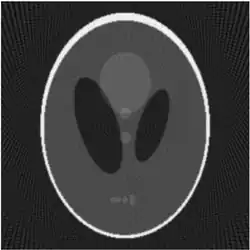

Zur Bewertung der bildgebenden Algorithmen werden Testbilder eingesetzt, wie nachfolgend an dem Shepp-Logan-Testbild dargestellt. Das Shepp-Logan-Testbild stellt eine Grafik dar, wie sie in ähnlicher Form in der medizinischen Diagnostik vorkommt, eine vereinfachte Schnittdarstellung durch den menschlichen Kopf: